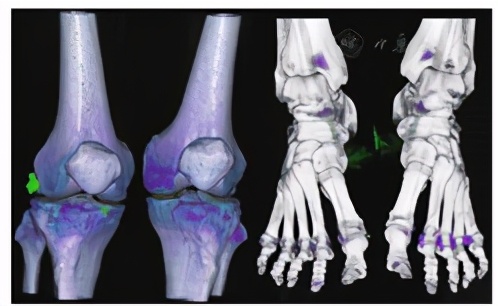

中国人民解放军南部战区总医院门诊及入院的相关检查:入院前3 d门诊空腹测尿酸628 μmol/L,入院后第7天测空腹尿酸525 μmol/L,门诊空腹血糖5.7 mmol/L。膝关节+踝关节CT示双侧髌股关节、左踝及左足骰骨-第4跖骨关节骨性关节炎表现;双膝、双踝及双足周围散在点状绿染结节,以右膝关节为甚,考虑少许痛风石形成(见图1)。双足超声示双侧第一跖趾关节表面有钙盐沉积(考虑痛风可能性大);双足疼痛处皮下距骨表面滑膜增生(见图2)。双下肢血管超声提示血流通畅。泌尿系超声示双肾有小结石。肾血流图提示肾功能轻度受损。血浆白蛋白、自身免疫的相关抗体、甲状腺功能指标、高敏肌钙蛋白和心电图均正常。入院后予以消炎、镇痛、碱化尿液、护胃抑酸等治疗,患者双下肢疼痛好转后加用降尿酸药物治疗;1周后患者病情稳定出院,嘱其纠正不良饮食习惯、多运动并继续降尿酸药物治疗;患者ED于泌尿外科门诊随诊,拟首选药物治疗,必要时结合患者意愿可行阴茎假体植入术。本例患者选择药物治疗ED,出院后随访3个月,ED未恢复。

图1 膝关节、踝关节的CT三维重建图像

Figure 1 3D reconstruction of CT images of knee and ankle joints of our case of gouty arthritis with erectile dysfunction